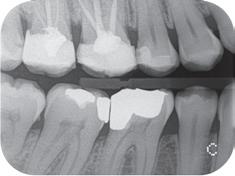

Skriver foto og røntgen i størrelse A6, postkortstørrelse, og gir eksepsjonelle utskrifter. For f.eks. henvisninger, til tanntekniker e.l.

Ypperlig til røntgen!